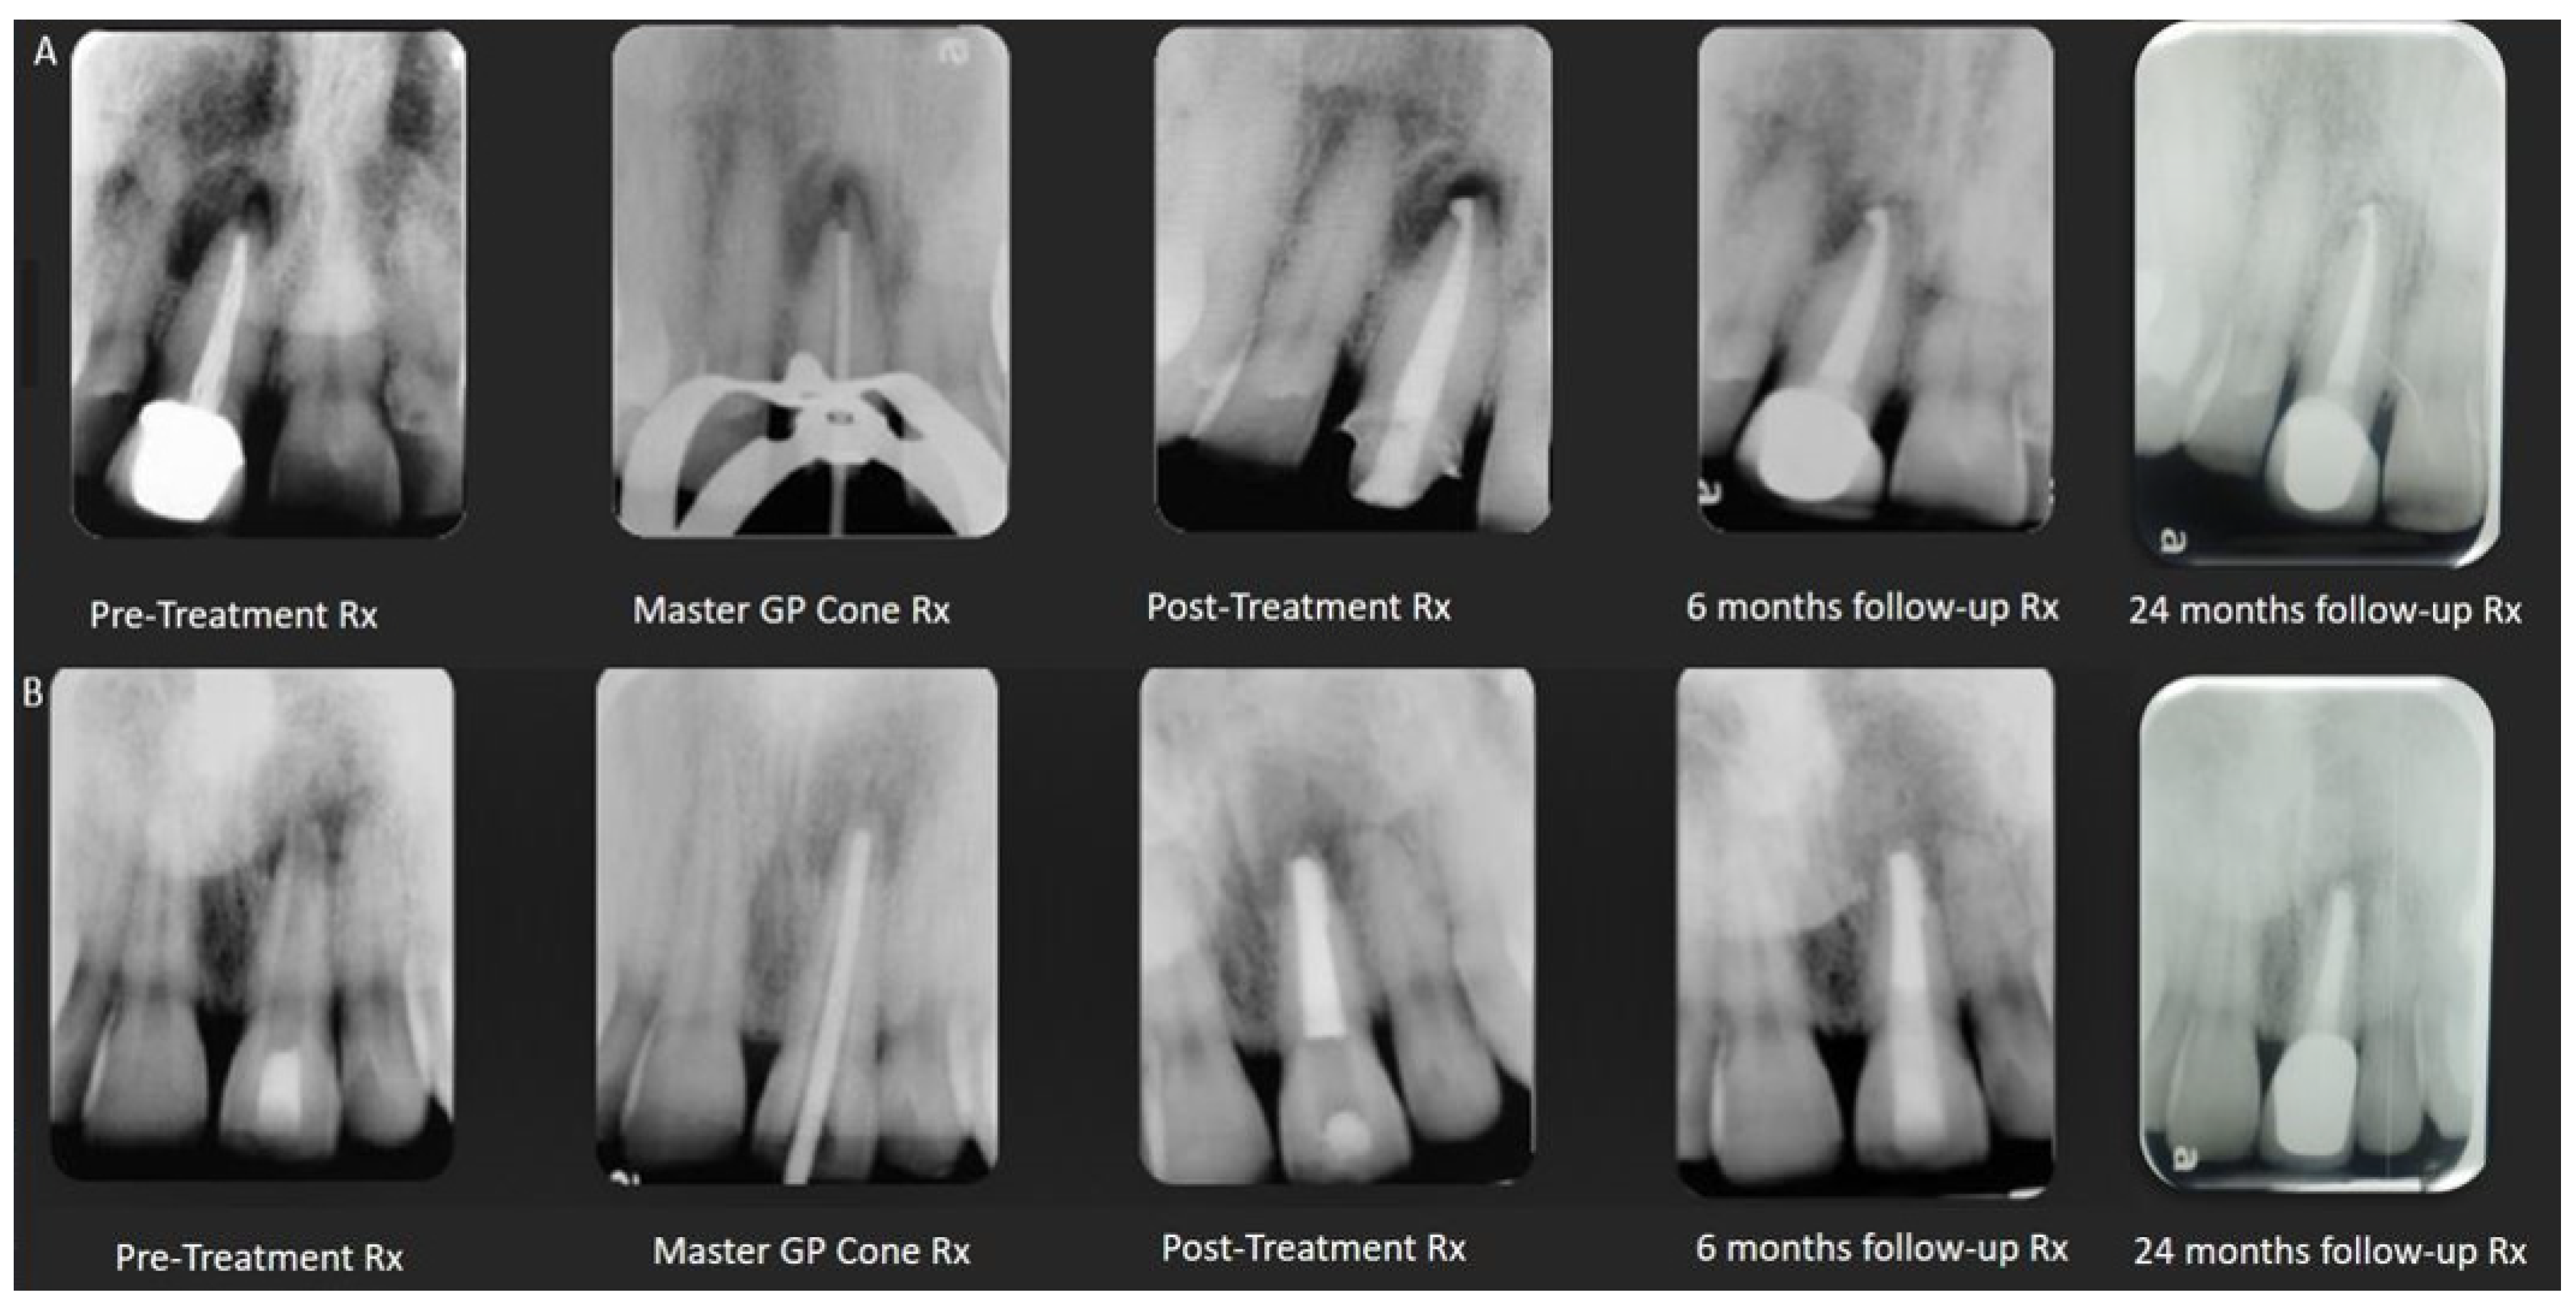

2.4. Resorptions

2.5. Non-Divergent Open Apex